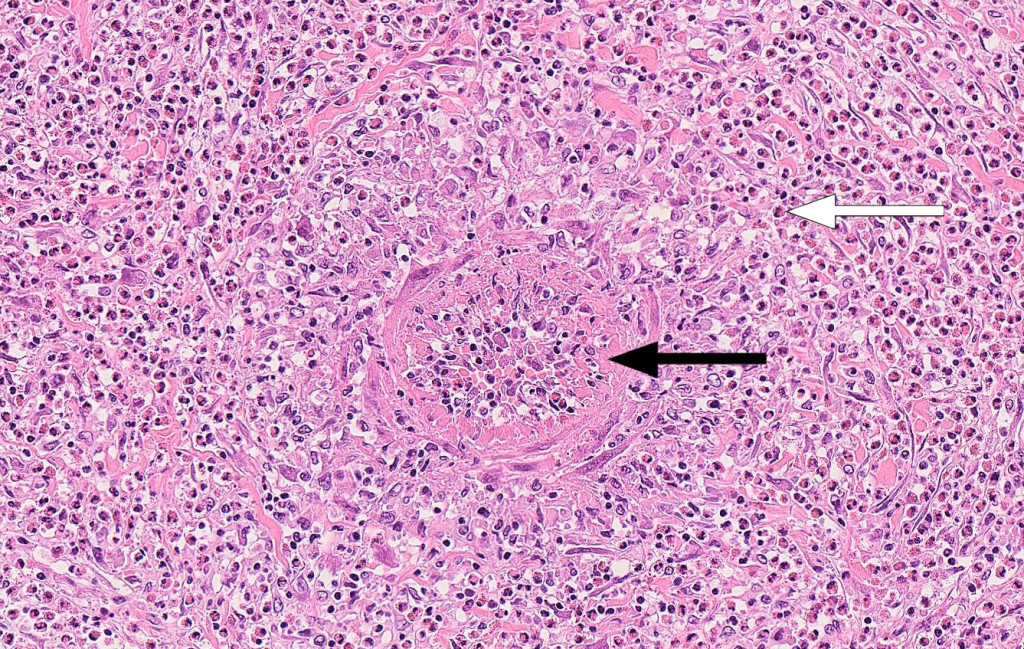

Autopsy revealed infiltration of eosinophilic granulocytes into the wall of the sagittal sinus. Neuropathological examination confirmed haemorrhagic infarction and venous sinus thrombosis. Histology sections taken from several organs revealed vasculitis with eosinophilic granulocytes in the walls of medium-sized arteries in the liver (Figure 2) and in an arterial branch in the meninges. These findings are consistent with eosinophilic granulomatosis with polyangiitis as the cause of the hypereosinophilic syndrome that was detected clinically.